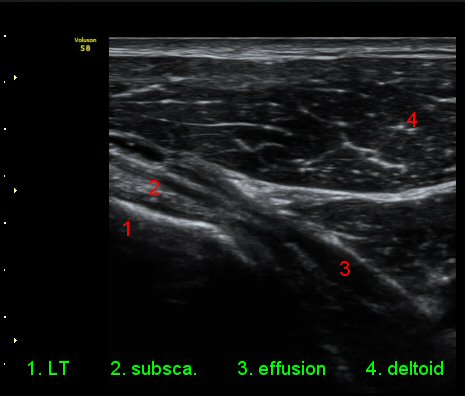

ÃÊÀ½ÆÄ °Ë»ç

ÀÌµÎ¹Ú±Ù°Ç È¾´Ü¸é°Ë»ç¿¡¼­ °ÇÁÖÀ§¿¡ ¼Ò·®ÀÇ ¼ö¾×Àú·ù¿Í Á¡¾×³¶³» ¾×Àú·ù°¡ °üÂûµÈ´Ù(»çÁø 1, 2).

ŽÃÊÀÚ¸¦ ¾à°£ ´Ù¸®ÂÊ, ³»ÃøÀ¸·Î À̵¿ÇÏ´Ï °ß°©ÇÏ±Ù°Ç Ç¥Ãþ¿¡ ¸¹Àº ¾çÀÇ ¼ö¾×Àú·ù°¡ °üÂûµÈ´Ù(»çÁø 3).